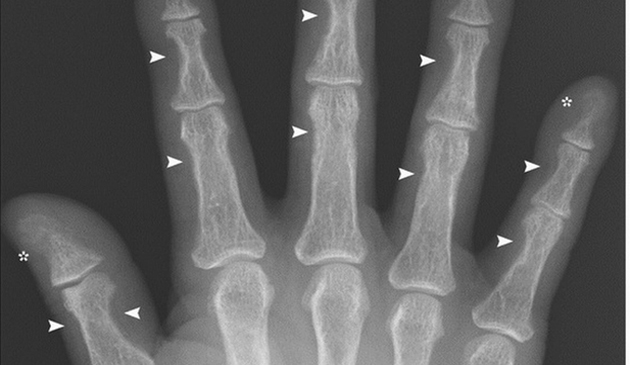

Cazul acestui bărbat a fost notat în manualele de medicină, pentru că rareori se întâlneşte o manifestare aşa de gravă a unei afecţiuni. Oasele lui par să fie pur şi simplu măcinate, mâncate, după cum se vede şi în radiografie.Pacientul este din Japonia şi are 45 de ani. El suferea de o tumoare benignă pe glandele paratiroide, care a provocat stimularea activităţii acestora. Din cauza bolii, glandele lui au produs prea mult hormon paratiroidian, care controlează nivelul de calciu din organism. Prin urmare, oasele lui au devenit foarte fragile, iar degetele de la mâini au început să se atrofieze, să se micşoreze. Din fericire, după ce bărbatul a fost operat şi tumoarea eliminată, nivelul de hormoni paratiroidieni a revenit imediat la normal.